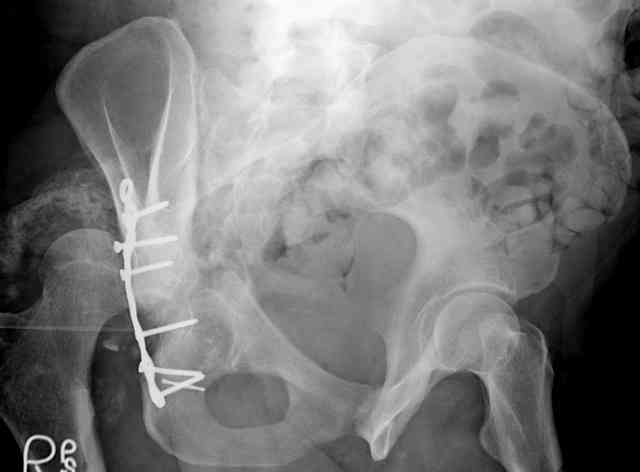

I'll include a few images of a similar injury in a similarly large male patient. This patient "showed up" in our ER c/o hip pain 2 months after being treated in the lateral position, without a quality reduction, without an anterior column transverse supporting implant, with an unbalanced plate applied too medially, with insufficient caudal segment fixation...it took over 8 hours and a 3+ l blood loss to debride the callus from front then

back, excise the HO, release his sciatic nerve, reduce the head-transverse-wall, and fix it...and now it's a staging procedure.